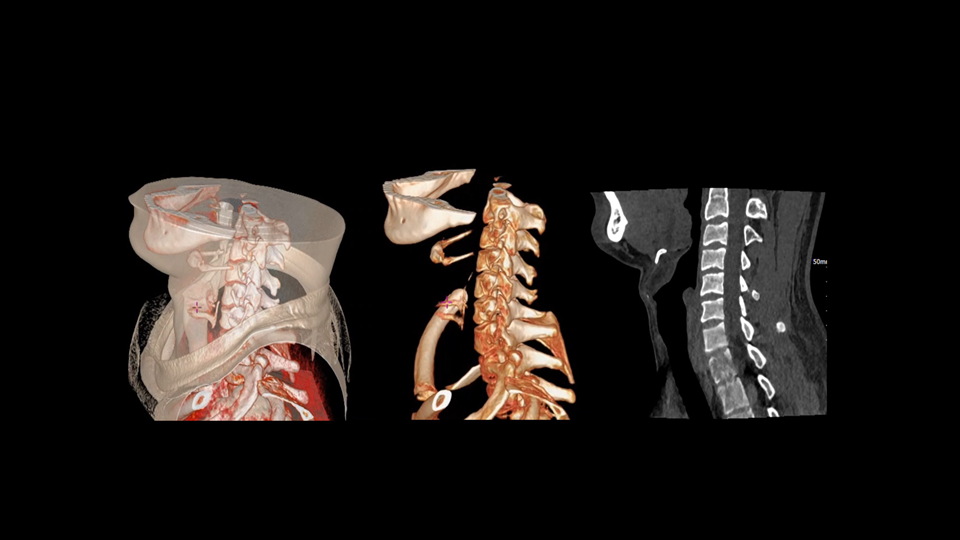

全身各部位动态CT成像

uCT SiriuX® 以全新双宽体系统架构,同步实现超高时间分辨率与宽体容积覆盖兼得,全面释放性能潜能,敏锐捕捉人体生理运动全景,带来动态影像新视角。

uCT SiriuX® 以16cm超宽Z轴覆盖,使超高时间分辨率应用于完整器官成像。无论是心脏搏动还是关节运动,整个目标区域可在同一瞬时被完整、清晰地捕捉,彻底消除时序误差,实现从“局部瞬间”到“全器官瞬时”的成像跨越。